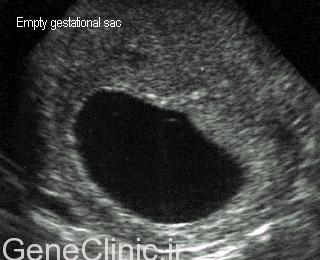

حاملگی پوچ زمانی اتفاق می افتد که یک تخمک بارور شده به جدار رحم می چسبد اما جنین تشکیل نمی شود. سلول ها از کیسه بارداری تکامل خواهند یافت اما جنین تشکیل نمی شود. حاملگی پوچ در سه ماهه اول اتفاق می افتد که معمولا زمانیست که زن از بارداری خود مطلع نیست. در بسیاری موارد این امر نهایتا منجر به سقط خواهد شد.

معمولا علایم حاملگی مثل عقب افتادن عادت ماهیانه و یا حتی مثبت شدن تست حاملگی اتفاق می افتد. و بسیاری از موارد خانم های مبتلا حتی فکر می کند هم چیز بر وفق مراد است و متوجه مشکل نمی شوند چرا که افزایش سطح سرمی hCG نیز مشاهده می شود. جفت تا مدتی به رشد خود بدون حضور جنین ادامه می دهد. تشخیص معمولا زمانی اتفاق می افتد که در سونوگرافی رحم خالی و یا کیسه حاملگی بدون جنین مشاهده می شود. درد خفیف شکمی و لکه بینی یا خونریزی خفیف واژینال گاها مشاهده می شود.